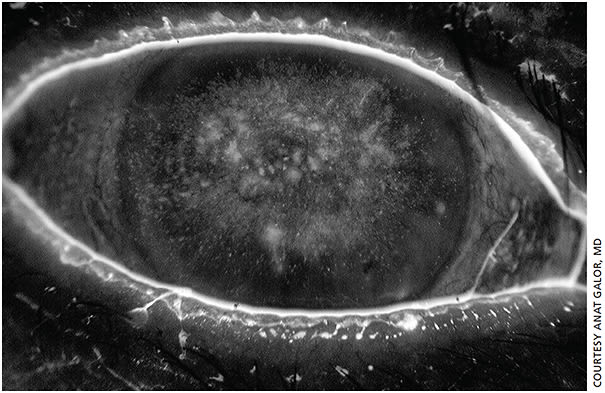

Corneal staining. There is no specific ocular surface finding that indicates asymptomatic dry eye — the only indication is that the patient does not have symptoms, yet the physician sees something on the ocular surface: an increase in tear evaluation, a decrease tear production, staining, and so on.

When a terrible ocular surface contradicts the patient’s claim of “feeling fine,” Dr. Galor looks for diabetic neuropathy and corneal nerve status. She will ask about chronic eyedrop use, because the common preservative, benzalkonium chloride (BAK), contributes to nerve damage.2 She also performs clinical tests to grade corneal sensation, or any difference between the patient’s eyes or both. She will also conduct confocal microscopy to evaluate nerve parameters, including density and tortuosity.